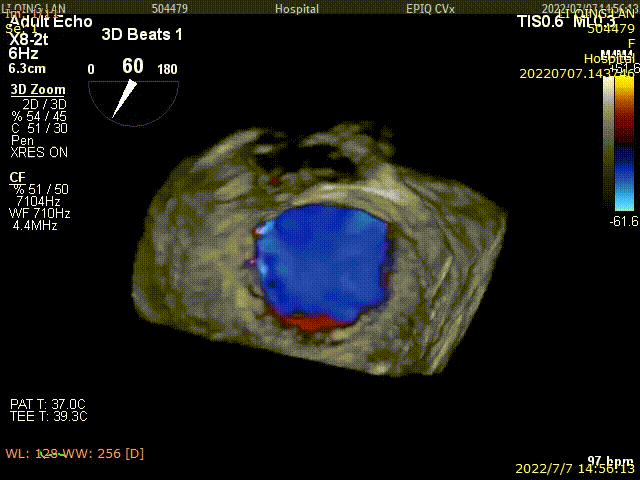

术后TEE显示,二尖瓣双孔化形成,反流明显减少